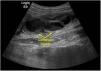

Niña de 11 años con síndrome de Down, que acude a urgencias por presentar dolor abdominal de predomino en fosa ilíaca derecha (FID) y fiebre de 48h de evolución. Entre los antecedentes encontramos enfermedad de Hirschsprung tratada mediante colostomía en el período neonatal y posterior descenso abdominoperineal tipo Duhamel, presentando varios episodios de oclusión intestinal posteriores que se resolvieron con tratamiento conservador. A su llegada presentaba regular estado general, fiebre de 39°C, el abdomen era blando y depresible, con dolor intenso y defensa muscular a la palpación de la FID. La analítica sanguínea demostró leucocitosis con neutrofilia y una PCR de 15,5mg/dl. Se realizó ecografía abdominal objetivándose una estructura tubular fija en la FID con paredes engrosadas y contenido líquido (figs. 1 y 2). El estudio se completó con una TAC abdominal confirmándose el diagnóstico de hidropiosalpinx derecho (fig. 3). Se inició antibioterapia endovenosa con amoxicilina-clavulánico objetivándose mejoría clínico-radiológica en las primeras 24h sin precisar drenaje quirúrgico de la colección. Se dio de alta a las 72h con antibioterapia oral y buena evolución posterior.

El hidropiosalpinx es una condición extremadamente rara en adolescentes sexualmente inactivas1. En este caso, debido a su rara asociación con la enfermedad de Hirschsprung, deben considerarse 2 hipótesis etiopatogénicas: origen secundario a la posible existencia de bridas intestinales por el antecedente de cirugía abdominal, o bien, un origen congénito en el contexto de neurocristopatía2,3. En cualquier caso, debe considerarse el hidropiosalpinx dentro del diagnóstico diferencial de abdomen agudo en las pacientes adolescentes, especialmente en aquéllas con historia de aganglionismo.